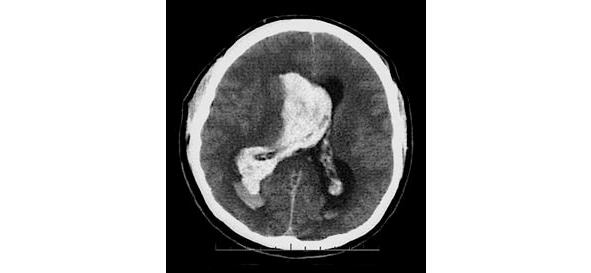

Среди геморрагических вариантов ОНМК выделяют: паренхиматозное кровоизлияние, вентрикулярное кровоизлияние, паренхиматозно-вентрикулярное кровоизлияние (рис. 3), а также субарахноидальное кровоизлияние.